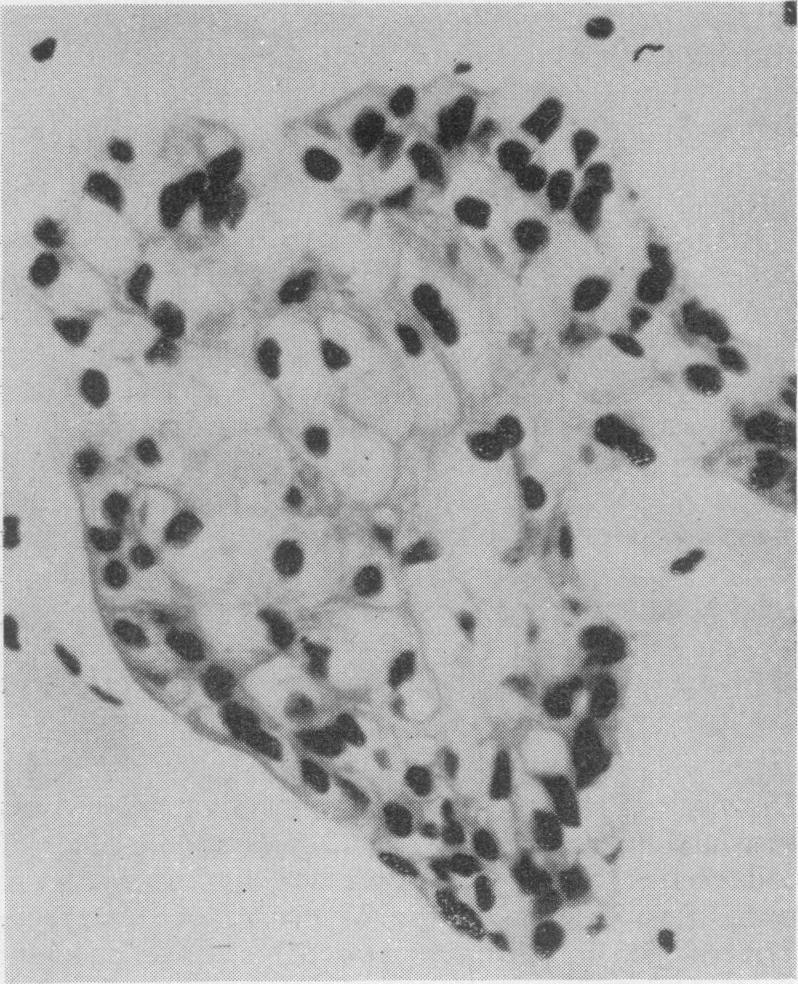

The oral changes in gargoylism.

Proc R Soc Med. 1962 Dec;55(12):1066-70. doi: 10.1177/003591576205501222.